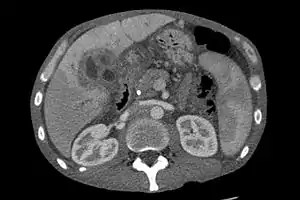

Ultrasound of the liver and biliary tree is often used as the initial imaging modality in people with suspected obstructive jaundice.[48][49] Ultrasound can identify obstruction and ductal dilatation and, in some cases, may be sufficient to diagnose cholangiocarcinoma.[50] Computed tomography (CT) scanning may also play an important role in the diagnosis of cholangiocarcinoma.[51][52][53]

Imaging of the biliary tree

While abdominal imaging can be useful in the diagnosis of cholangiocarcinoma, direct imaging of the bile ducts is often necessary. Endoscopic retrograde cholangiopancreatography (ERCP), an endoscopic procedure performed by a gastroenterologist or specially trained surgeon, has been widely used for this purpose. Although ERCP is an invasive procedure with attendant risks, its advantages include the ability to obtain biopsies and to place stents or perform other interventions to relieve biliary obstruction.[12] Endoscopic ultrasound can also be performed at the time of ERCP and may increase the accuracy of the biopsy and yield information on lymph node invasion and operability.[54] As an alternative to ERCP, percutaneous transhepatic cholangiography (PTC) may be utilized. Magnetic resonance cholangiopancreatography (MRCP) is a non-invasive alternative to ERCP.[55][56][57] Some authors have suggested that MRCP should supplant ERCP in the diagnosis of biliary cancers, as it may more accurately define the tumor and avoids the risks of ERCP.[58][59][60]